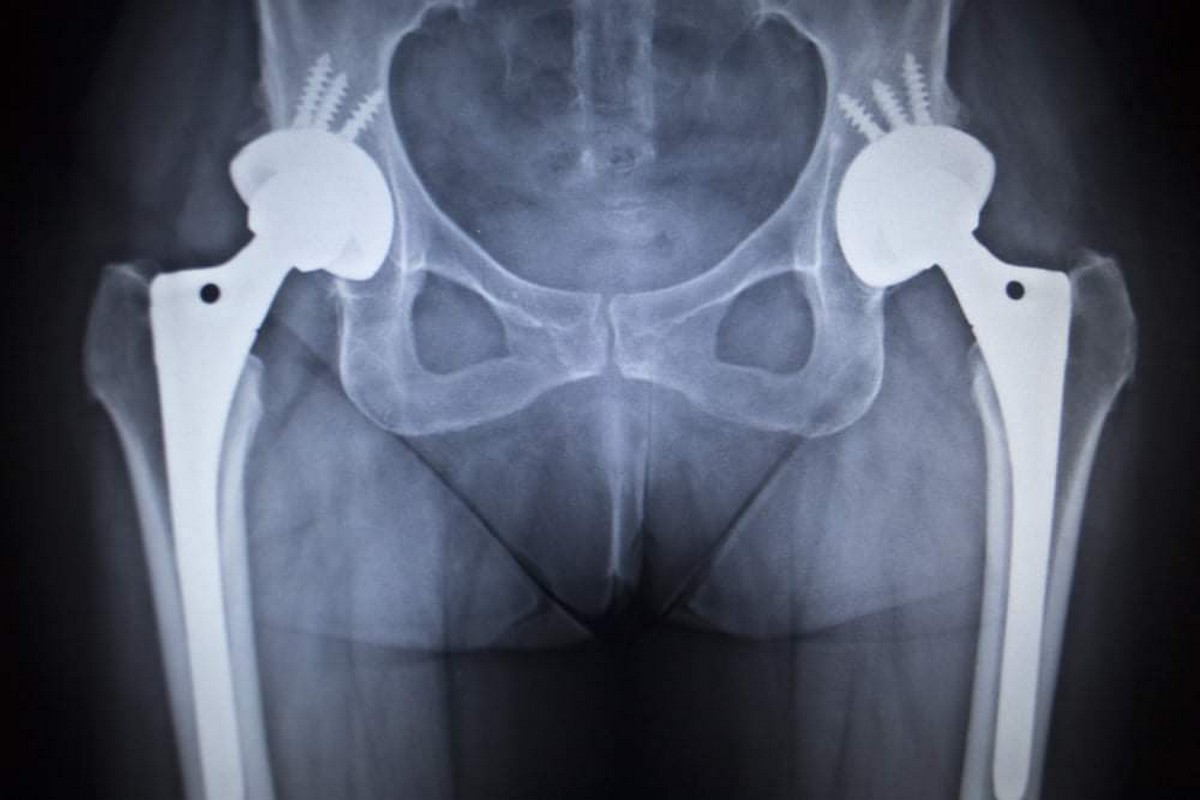

Zwyrodnienie stawów zostało uznane przez WHO za chorobę cywilizacyjną. Szacuje się, że co trzeci z seniorów będzie wymagał przeprowadzenia zabiegu wszczepienia endoprotezy stawu biodrowego. W Polsce systematycznie wzrasta liczba zrealizowanych endoprotezoplastyk. W przypadku stawu kolanowego z 4072 w roku 2005 do 27 653 w 2017, a stawu biodrowego z 26 091 do 56 688. W 2018 roku w całym kraju wykonano 56 983 endoprotezoplastyk stawu biodrowego oraz 29 950 endoprotezoplastyk stawu kolanowego.

W celu osiągnięcia dobrego stanu zdrowia w jak najkrótszym czasie powinno wdrażać się programy zintegrowanej opieki okołooperacyjnej dla dorosłych po endoprotezoplastyce. Inną zaletą takich programów jest zmniejszenie kosztów ponoszonych zarówno przez pacjenta, jak NFZ i ZUS, a także lepsze wykorzystanie zasobów bez utraty jakości opieki i satysfakcji pacjentów. Zintegrowane programy opieki łączą w sobie zarówno przygotowanie przedoperacyjne, śródoperacyjne metody opieki oraz opiekę pooperacyjną, gdzie aktywnymi uczestnikami są zarówno pacjenci, jak i lekarze, anestezjolodzy, pielęgniarki, fizjoterapeuci oraz terapeuci zajęciowi. W wielu badaniach wykazano, że zintegrowany program opieki skraca długość pobytu w szpitalu, obniża częstość powikłań, a także przyczynia się do poprawy funkcji stawów w okresie pooperacyjnym. Ważnym argumentem przemawiającym za takim rozwiązaniem jest również fakt, że najliczniejszą grupą pacjentów, u których wykonuje się te zabiegi, są osoby w wieku 50-69 lat (49% w przypadku stawu biodrowego i 53% kolanowego). Są to w większości osoby czynne zawodowo, dlatego konieczne jest zapewnienie szybkiej i sprawnej opieki umożliwiającej im powrót do pracy.